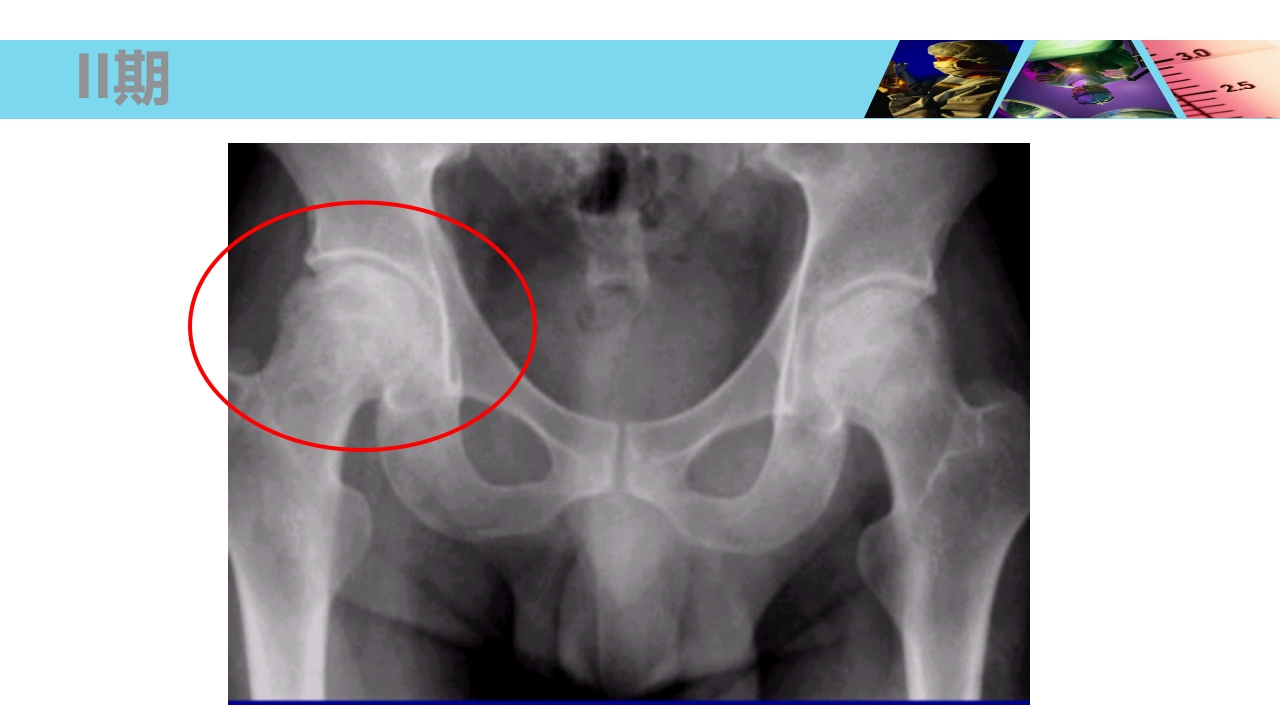

股骨头无菌性坏死 Necrosis of Femoral Head xxxx医院 骨科 WHO/WHAT/WHY/HOW? OUTLINE 1 2 3 4 5 概念及流行病学 病因 发病机制及病理 临床表现及诊断 治疗 概 念 Concept 股骨头坏死、股骨头缺血性坏死、股骨头无菌性坏 死等(Necrosis of Femoral Head) 不同病因破坏了股骨头血供所造成的最终结果。 损伤-修复(Damage-Repair) 4 股骨头血供 由旋股内、外侧动脉所发出的支持带动脉,占股骨头血供的70%。 股深动脉所发出的股骨滋养动脉,占股骨头血供的25%。 闭孔动脉或旋股内侧动脉所发出的股骨头韧带动脉,占股骨头血供的5%。 股骨头血供 一、流行病学 Epidemiology 世界骨科三大难题之一 在美国,年人均发生率在 2 万 -3 万之间,约有 5%-12% 的髋关 节置换...